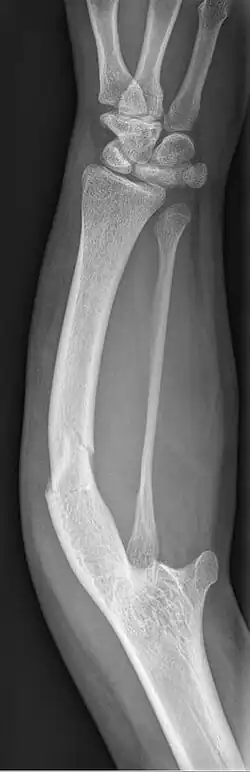

Ulnar dysplasia also known as ulnar longitudinal deficiency, ulnar club hand or ulnar aplasia/hypoplasia is a rare congenital malformation which consists of an underdeveloped or missing ulnae bone, causing an ulnar deviation of the entire wrist. The muscles and nerves in the hand may be missing or unbalanced. In severe cases, ulnar digits (e.g. ring and pinky finger) may be missing. Sometimes, radial dysplasia occurs alongside this malformation.[2] This condition occurs in 1 in 100,000 live births.[3][4][5][6] Sometimes, other orthopedic problems occur alongside this malformation, such as scoliosis.[7]

Type 2: The ulnae is moderately-severely smaller than normal. The radius is deviated and so is the hand

Type 3: The ulnae is completely missing. The radius is even more deviated, causing a severe ulnar deviation of the hand.

Type 4: The most severe type of ulnar dysplasia, the ulnae is completely missing, and the wrist is severely deviated. The elbow bones are fused together, so the elbow has reduced mobility